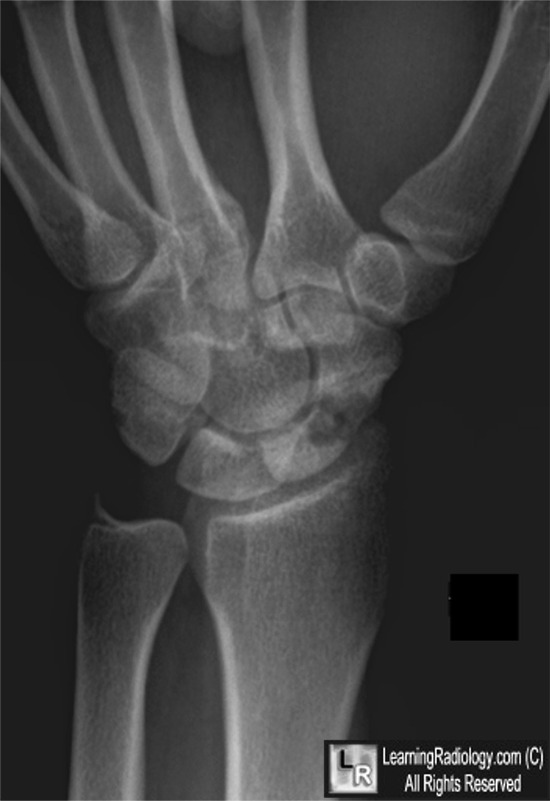

Avascular necrosis of the scaphoid secondary to fracture. Both photos: There is a transverse fracture of the waist of the scaphoid (yellow arrows) resulting in increased density of the proximal pole (white arrows) from avascular necrosis.

For these same photos without the arrows, click here and here